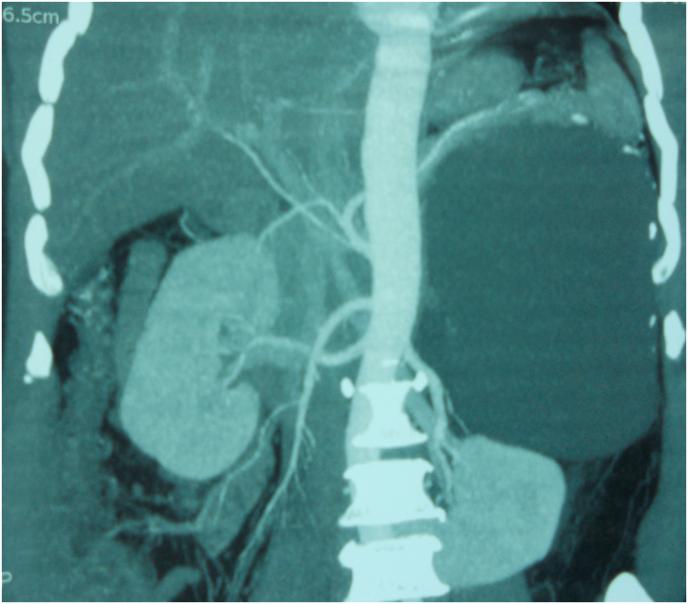

一例巨大肾上腺囊肿病例。

A case of a giant adrenal cyst.

Giant adrenal cysts represent rare clinical entities that are usually discovered incidentally. Here, we describe a patient who presented with nonspecific upper abdominal left pain. Imaging studies revealed a huge left adrenal cyst. Routine laboratory tests and endocrine function tests were all normal. The patient underwent surgery, and the cyst was completely removed with total adrenalectomy. Histological examination revealed a benign epithelial adrenal cyst.The postoperative course was uneventful and the patient had no evidence of recurrence during a 3-year follow-up. We discuss the diagnosis and management of adrenal cysts.

巨大肾上腺囊肿是罕见的临床病症,通常为偶然发现。在此,我们描述一名出现非特异性左上腹疼痛的患者。影像学检查发现一个巨大的左肾上腺囊肿。常规实验室检查和内分泌功能检查均正常。该患者接受了手术,囊肿通过肾上腺全切术被完全切除。组织学检查显示为良性肾上腺上皮囊肿。术后过程顺利,患者在3年随访期间无复发迹象。我们讨论了肾上腺囊肿的诊断和处理。